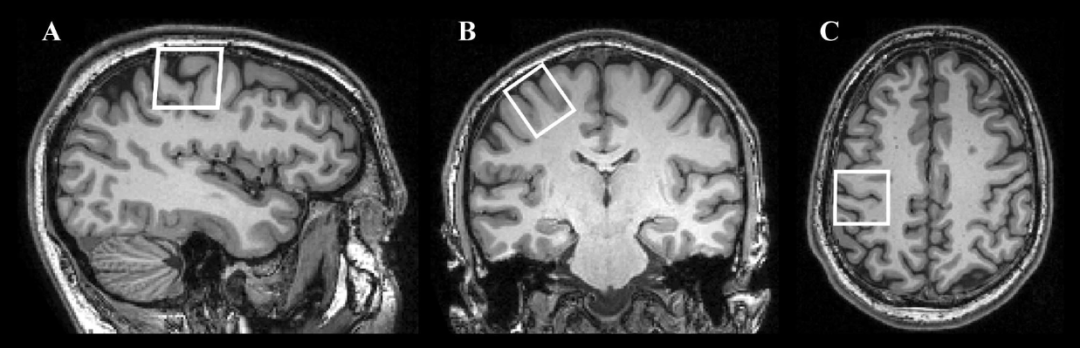

而神经学家则利用现代更清晰的大脑成像,对左撇子和右撇子进行了统计,看他们的左右大脑差异。

他们也找到了很有意思的结果:左撇子的左右脑差异相较于右撇子的更小,并且男性的这种差异更明显

左右脑在成像上一些显著的差异

(图源:Yousry et al.)